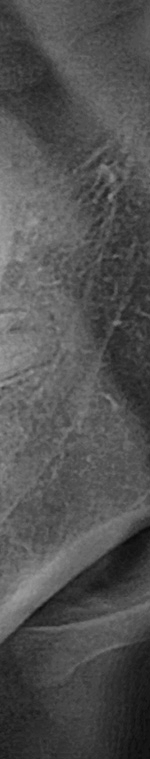

턱 뼈와 치아 사이에 공간이 충분하지 않기 때문에 누워서 올라오거나 매복되어 자라는 경우가 많았어요. 반포치과를 찾는 분들의 사랑니의 경우 매복된 경우도 많고 이가 완전히 잇몸 밖으로 나오지 않아서 일반 치과에서는 발치가 어려웠어요. 사랑니발치가 왜 필요한지 가끔 의문을 가지는 분이 계셨어요. 사랑니발치를 왜 해야 하는지 알려드리겠어요. 사랑니는 다른 치아처럼 바르게 나는 경우도 드물게 있긴 하지만 대부분 어금니 쪽으로 기울어져서 올라오거나, 완전히 수평으로 누워서 자라는 경우도 있었어요. 누워서 자라는 치아는 옆의 치아를 밀어 치열이 비뚤어지고 부정교합을 유발했어요.

사랑니가 90도로 누워서 난 경우는 수평 매복, 뼈나 잇몸에 사랑니가 완전히 덮여서 아예 보이지 않는 경우는 완전 매복, 일부분만 잇몸이나 뼈에 덮여있는 경우 부분매복이라고 했어요. 대부분의 환자분이 이런 매복 중에 한 가지에 해당하기 때문에 시술이 매우 어려웠어요. 특히 사랑니 주변으로는 구강과 관련된 중요한 신경 조직이 인접하여 있기 때문에 고난이도 시술이라고 할 수 있었어요.

사랑니발치를 하기 위해서는 먼저 파노라마 x선 사진을 통해 발치 시 신경에 영향을 줄 수 있는지 확인하는 과정을 진행했어요. 이 과정을 통해서 충분히 의사와 상담을 한 후 처방전을 발급했어요. 이 때 처방전에는 항생제를 포함하여 발치 후 통증을 대비한 진통제를 처방했어요. 환자에게 충분히 설명한 후에 국소마취를 진행하고 마취가 된 다음에 절개를 최대한 덜 하는 방향으로 수술하여 사랑니를 발치했어요.